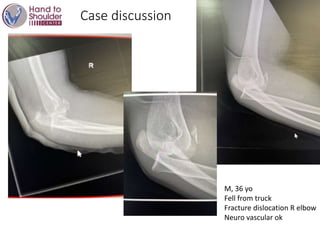

Case discussion

M, 36 yo

Fell from truck

Fracture dislocation R elbow

Neuro vascular ok

What do you do ?